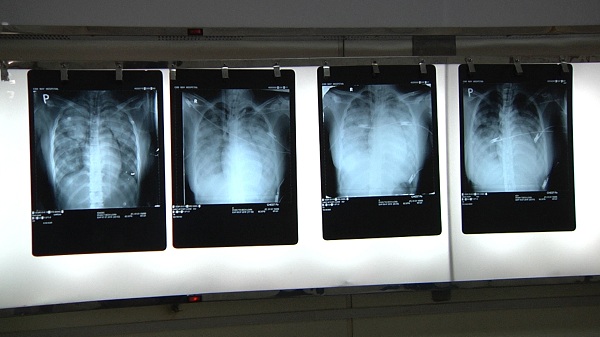

Hình ảnh X.quang Phổi của bệnh nhân cho thấy bệnh nhân bị phù phổi nặng

Đúng 2 giờ sáng ngày 7/7/2016, tại bệnh viện Chợ Rẫy, bệnh nhân nhập viện trong tình trạng rất nguy kịch, tri giác lơ mơ, huyết áp 60/30 mmHg, mạch nhanh, nồng độ oxy trong máu thấp, bóp bóng qua ống nội khí quản, suy hô hấp, phù phổi nặng. Bệnh nhân vật vã, tím tái và có nhiều máu trào ra từ ống nội khí quản.